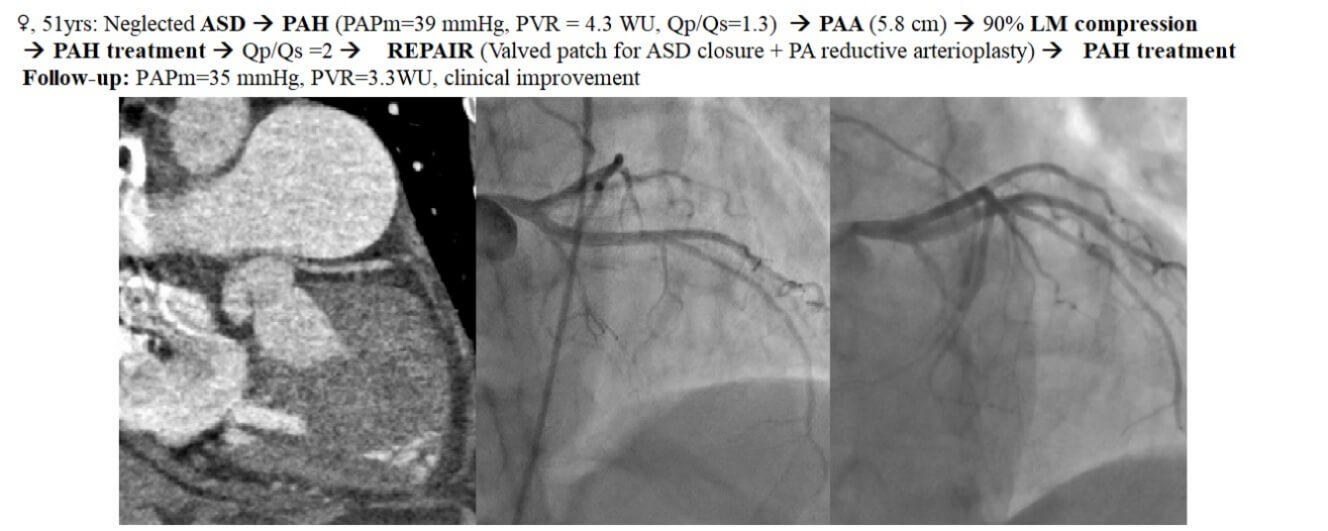

Left main coronary compression syndrome (LMCS) may complicate pulmonary artery aneurysms (PAA), usually developed in the context of pulmonary arterial hypertension (PAH). We report the case of a 51-year-old female patient with an atrial septal defect (unsuitable for device closure) complicated by a PAA generating a 90% left main stenosis. The significant PAH held us back from immediate surgery. After specific dual PAH-targeted therapy (sildenafil and bosentan), the atrial septal defect could be closed with a unidirectional valved patch; the PAA-induced LMCS was treated by reductive arterioplasty. The postoperative course was uneventful. Follow-up showed clinical improvement, but PAH treatment was still needed. After three months, coronary angiography showed only an insignificant residual left main stenosis, proving that reductive pulmonary arterioplasty was effective in treating LMCS. Any PAA requires further evaluation for LMCS, a dangerous but treatable complication. The “treat-repair-treat” strategy and shunt-closure with a unidirectional valved patch can both improve surgical prospects of LMCS with shunt-related PAH.Graphic Abstract